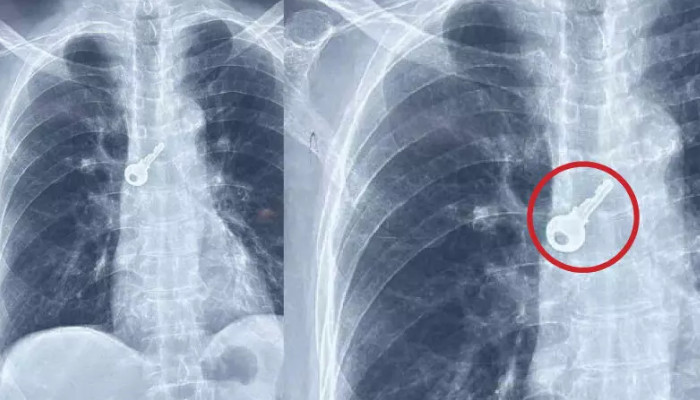

ശ്വാസനാളത്തിൽ കുടുങ്ങിയ താക്കോൽ ബ്രോങ്കോസ്കോപ്പി പരിശോധനയും ശസ്ത്രക്രിയയും നടത്തി പുറത്തെടുത്തു. ആലപ്പുഴ മെഡിക്കൽ കോളജ് ആശുപത്രിലെത്തിയ വയോധികന്റെ ശ്വാസകോശത്തില് നിന്നാണ് ഡോക്ടർമാർ താക്കോൽ പുറത്തെടുത്തത്. ഹരിപ്പാട് ലക്ഷ്മി ഭവനത്തിൽ ചെല്ലപ്പൻപിള്ളയുടെ (77) ശ്വാസനാളത്തിലാണ് താക്കോല് കുടുങ്ങിയത്. രണ്ടുമണിക്കൂർ നീണ്ട ശസ്ത്രക്രിയയായിരുന്നു.

ചൊവ്വാഴ്ച വീട്ടിൽ ബോധമറ്റു വീണ ചെല്ലപ്പൻ പിള്ളയെ വീട്ടുകാർ ഉടൻ മെഡിക്കൽ കോളജ് ആശുപത്രിയിൽ എത്തിക്കുകയായിരുന്നു. ശ്വാസതടസ്സവും ചുമയും അനുഭവപ്പെട്ട ഇദ്ദേഹത്തെ എക്സ്-റേ പരിശോധനക്ക് വിധേയനാക്കിയപ്പോഴാണ് താക്കോൽ ശ്വാസനാളത്തിൽ കുടുങ്ങിയത് അറിയുന്നത്. എന്നാല് താക്കോൽ എങ്ങനെ ഉള്ളിൽപോയെന്ന് അറിയില്ലെന്ന് ചെല്ലപ്പൻ പിള്ള പറഞ്ഞു. പുറത്തെടുത്ത താക്കോൽ അടുത്ത ദിവസങ്ങളിൽ ഉള്ളിൽ പോയതല്ലെന്നും മാസങ്ങളുടെ പഴക്കമുണ്ടെന്നും ഡോക്ടർമാർ പറഞ്ഞു.